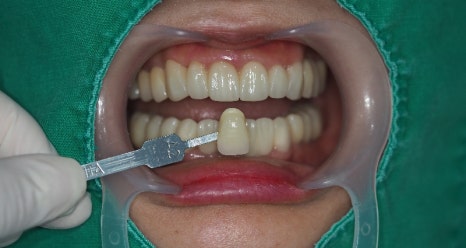

이렇게 전치부 앞쪽 치아들은 심미적인 부분과 기능적인 부분 두가지가 충족이 되어야 하기에

PMMA (수정 할 수 있는 최종 전 보철) 사용해보시면서 환자분의 주변 치아 색상과도 어우러 질 수 있도록

원하시는 모양이나 피드백들을 받아 최종적으로 제작 하게 됩니다.